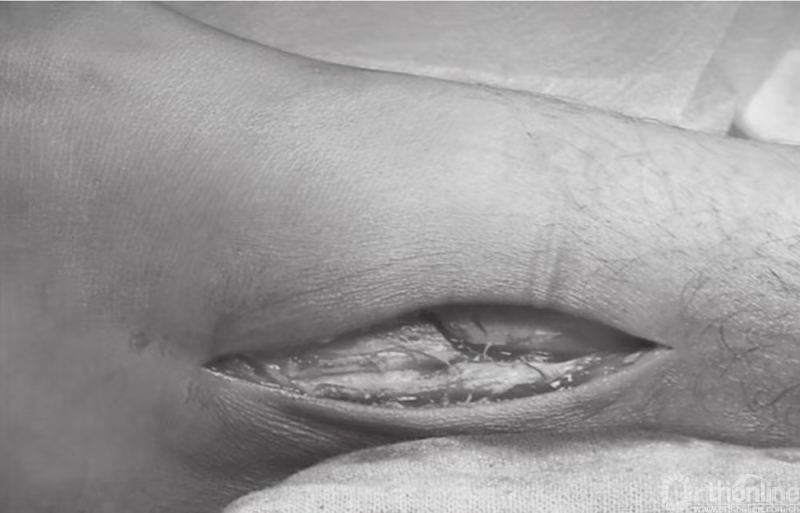

内踝骨折中通常会伴有骨膜撕裂(图11)。这些骨折病例大多数均存在骨膜的介入,这便造成了愈合困难,可能导致骨不连。应将骨膜抬离骨折端,并清理折断表面的血块。将骨折片向远端回缩,以观察关节。在移除关节内所有的游离骨块后,用盐水清洗关节(图12)。

图11 骨膜撕裂及骨折间隙